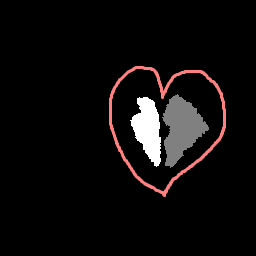

We develop this project to solve the problem of identifying where the brain stem and cerebellum are in a given MRI. By finding or, in the language of the field, by segmenting the brain stem and cerebellum, we find the most relevant regions to look at brain movement. Using the DENSE MRI data, we can then average the movement over those regions to produce a biomarker that can help predict whether or not a patient has the Chiari Malformation. By producing these segmentations (examples above) automatically with the machine learning or atlas-based approaches, the diagnosis process could become much cheaper and more efficient.

We develop this project to solve the problem of identifying where the brain stem and cerebellum are in a given MRI. By finding or, in the language of the field, by segmenting the brain stem and cerebellum, we find the most relevant regions to look at brain movement. Using the DENSE MRI data, we can then average the movement over those regions to produce a biomarker that can help predict whether or not a patient has the Chiari Malformation. By producing these segmentations (examples above) automatically with the machine learning or atlas-based approaches, the diagnosis process could become much cheaper and more efficient.